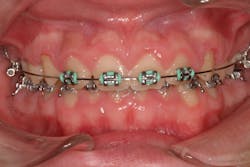

One reason people develop gummy smiles is inflammatory-induced gingival enlargement, typically caused by biofilm (bacteria) and the host response. Gum disease (gingivitis and periodontitis) can result in gum tissue swelling, redness, gum overgrowth, and bleeding (figure 1). In addition to bacterial infiltration of the gums due to poor oral hygiene, orthodontic appliances have been associated with gingival enlargement since braces can act as food traps (figure 2).Further reading: Considerations when using veneers to fabricate a perfect smile